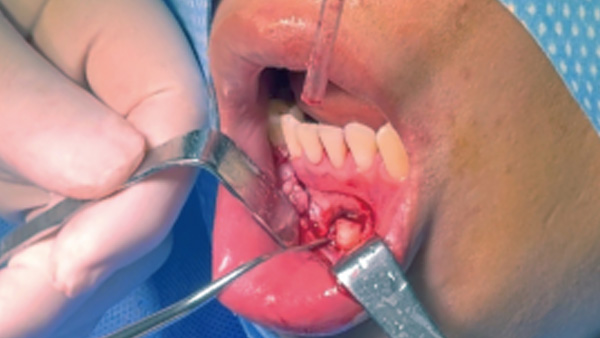

覆蓋所有牙位、即刻種植、即拔即種、全口無牙頜種植